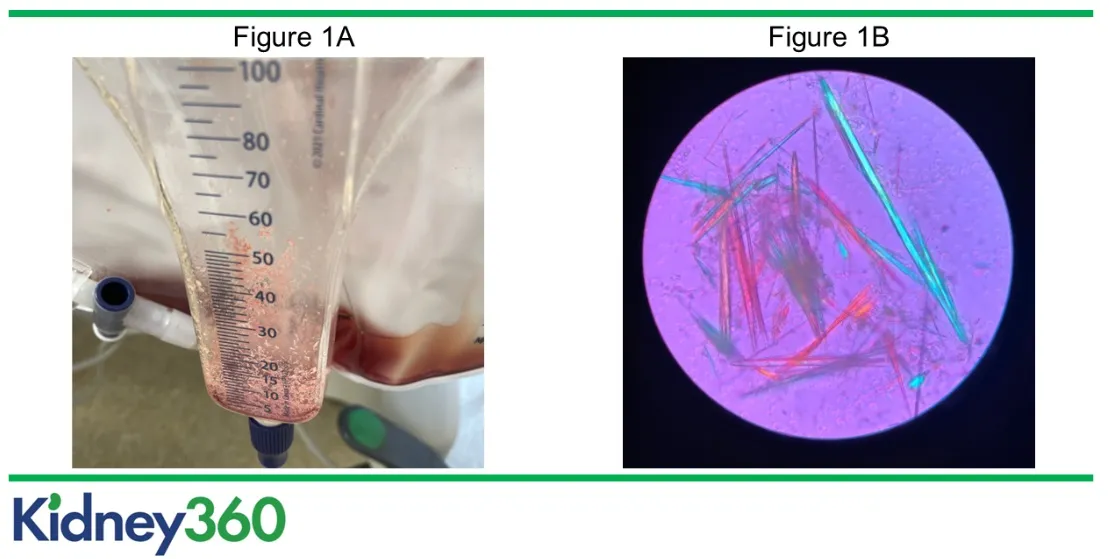

Você já viu um efluente de diálise vermelho? U0001F6A8 Neste caso surpreendente, a coloração da bolsa ajudou a confirmar um diagnóstico crítico. Saiba como diferenciar causas, conduzir o caso e evitar armadilhas diagnósticas.

Confere esse caso de mudança de coloração no efluente do dialisato em um paciente em diálise contínua